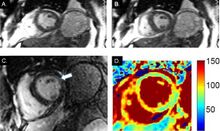

Cardiovascular magnetic resonance in wet beriberi

Wet beriberi affects the heart and circulatory system. It is sometimes fatal, as it causes a combination of heart failure and weakening of the capillary walls, which causes the peripheral tissues to become edematous. Wet beriberi is characterized by: